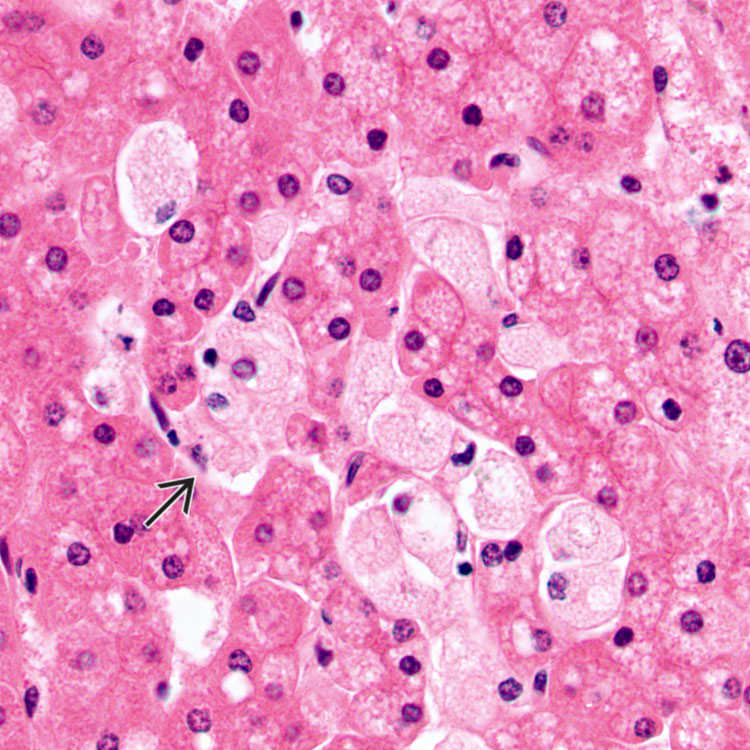

Болезнь Нимана-Пика Тип А: Симптомы и лечение

Раздел: Визуальный дайджест